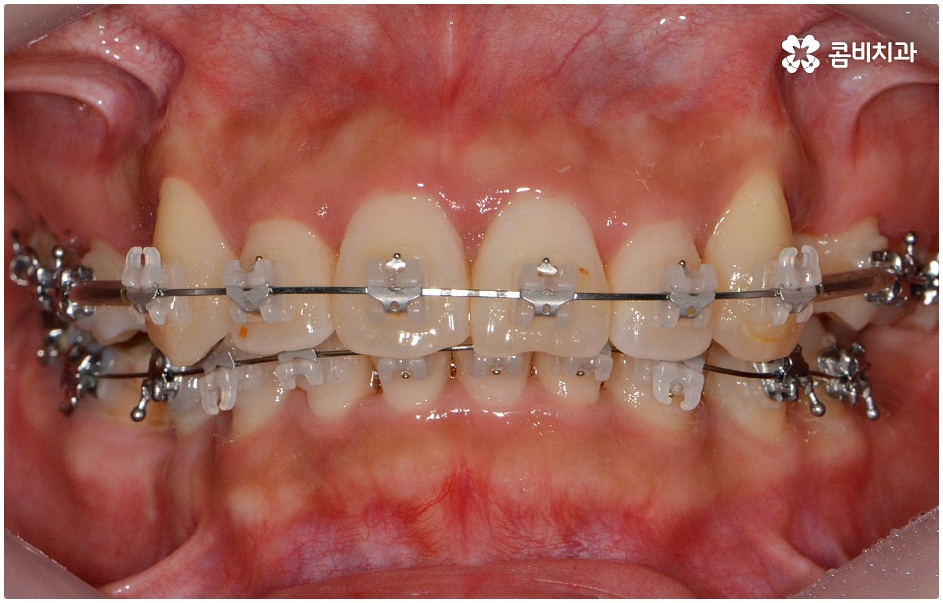

치료를 위해서는 입을 안쪽으로 넣기 위한 공간을 확보해야 하므로 보통 위아래 소구치 총 4개의 치아를 발치하여 그 공간을 활용해 튀어나온 치아와 잇몸을 전체적으로 뒤로 이동시키는 방법을 사용하나 최근에는 미니스크류, 치간 삭제 등의 방법을 이용하여 비발치 교정을 진행하기도 하니 먼저 자신의 상황을 꼼꼼하게 살펴보고 부정 교합의 원인과 정도부터 정확하게 파악하는 것이 필요한 거에요.

또한 골격성으로 유발된 문제의 경우 치료가 끝나고 사후 관리를 제대로 하지 않으면 다시 원래대로 돌아가려는 힘이 강하니 주기적으로 체크를 하면서 교정 유지장치를 일정 시간 이상 꼭 착용하시는 것을 권유드리며 탈착식 외에 치아 뒷면에 얇게 부착하는 방식의 유지 장치도 있으니 담당의 선생님께 문의해 보시고 각자에게 맞는 것으로 사후 관리를 철저하게 해 주시길 바라고 있습니다.